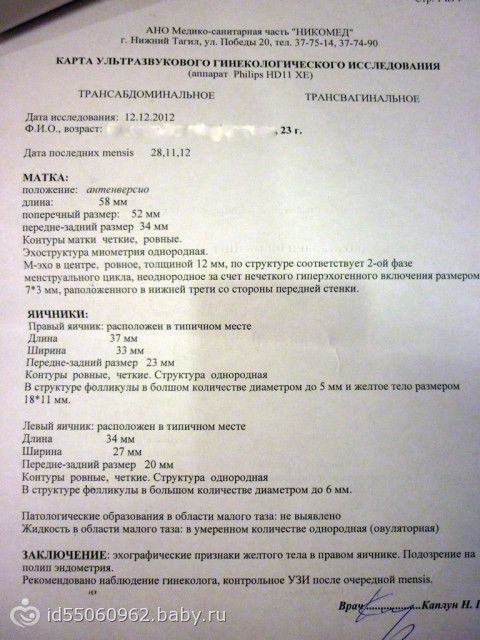

Медицинская диагностика: Гиперплазия эндометрия на УЗИ

Раздел: Мудрость в объективе